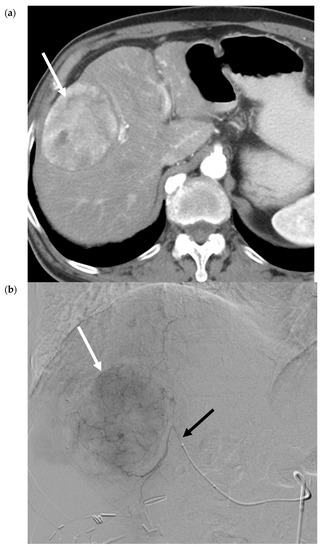

- Vouche, M.; Lewandowski, R.J.; Atassi, R.; Memon, K.; Gates, V.; Ryu, R.K.; Gaba, R.C.; Mulcahy, M.F.; Baker, T.; Sato, K.; et al. Radiation lobectomy: Time-dependent analysis of future liver remnant volume in unresectable liver cancer as a bridge to resection. J. Hepatol. 2013, 59, 1029–1036. [Google Scholar] [CrossRef]

- Teo, J.-Y.; Allen, J.C.; Ng, D.C.; Choo, S.-P.; Tai, D.W.; Chang, J.P.; Cheah, F.-K.; Chow, P.K.H.; Goh, B.K.P. A systematic review of contralateral liver lobe hypertrophy after unilobar selective internal radiation therapy with Y90. HPB 2015, 18, 7–12. [Google Scholar] [CrossRef]